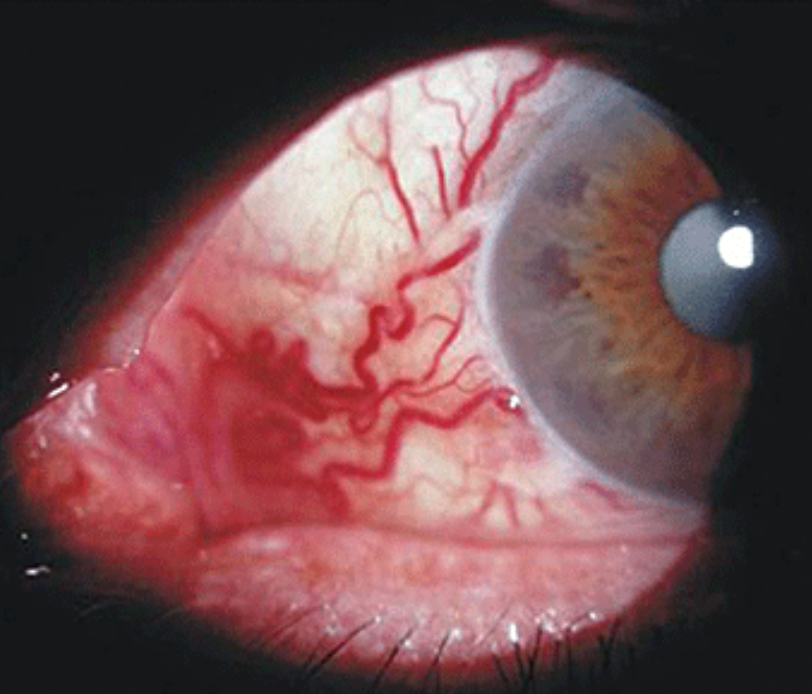

Angioma episcleral/conjuntival

Quadro unilateral de aumento do calibre e tortuosidade dos vasos episclerais, aumento da PVE e aumento da PIO

Idiopático, sem causas secundárias